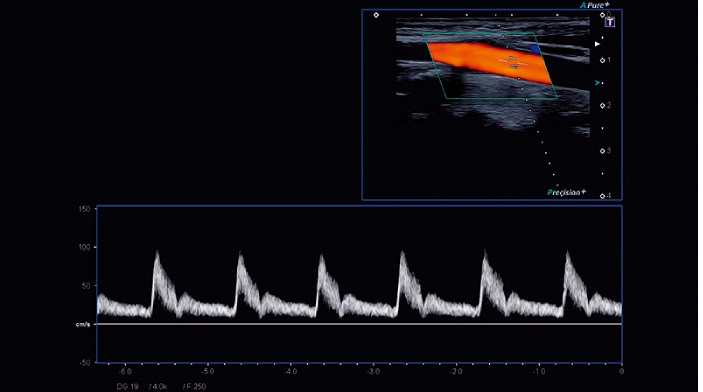

- SMI - опция, упрощающая визуализацию микроциркуляторного русла. С ее помощью обследуются сосуды с низкой интенсивностью кровотока, изучаются наиболее тонкие структуры. SMI упрощает диагностику новообразований, минимизирует вероятность ошибки

- Линейный (до 15 МГц)

- Линейный низкочастотный (до 10 МГц)

- Линейный высокочастотный (до 18 МГц)

- Линейный ультравысокочастотный (от 18 МГц)